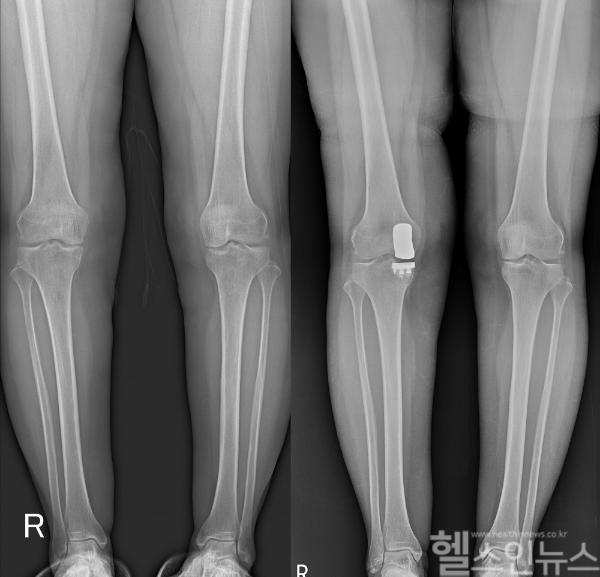

그렇다면 이른 나이에 퇴행성관절염 말기에 다다른 50대~60대 초반 환자들은 어떻게 하는 것이 좋을까? 여러 가지 방법 중에서도 눈에 띄는 대안은 ‘인공관절 부분치환술’이다. 부분치환술은 말 그대로 손상된 부분만 인공관절로 교체해주는 수술법으로 자기 관절을 보존하는데 좋다. 전체를 교체하는 전치환술에 비해 수술 부위가 5-7cm로 작고 회복이 빠르다. 입원기간 역시 짧고 일상이나 직장으로의 복귀가 빠르다는 장점이 있다. 그리고 무엇보다 자기 관절을 보존하기 때문에 정상 관절과 비슷하게 무릎을 구부릴 수 있고, 계단을 오르고 내릴 시 평형감각(Proprioception)을 유지하는 십자인대를 보존하기 때문에 편안함과 안정성을 느낄 수 있다.

다만 부분인공관절 수술은 기존 인공관절 전치환술보다 까다로운 수술로 무릎 관절을 구조물들의 원래 위치를 파악하고 환자의 관절 기능 향상을 위해 정밀한 검사를 통해 위치를 설정해 수술이 이뤄져야 한다. 정확한 수술이 이뤄지지 않으면 빠르면 몇 년 안에도 마모가 돼 전치환술을 하는 경우가 있기 때문에 잘 권유하지 않는 경향이 있다. 통계에 의하면 인공관절 수술 건수 중 10% 정도가 부분 인공관절 수술의 적응증이 될 수 있고, 고령화로 인해 더 늘어날 것으로 예상되고 있지만 수술의 까다로움과 수술 과정이 어렵다는 이유로 현실적으로는 많이 이뤄지지 않고 있는 것이다.

세계적 학술지인 ‘The Knee’에 게재된 ‘인공슬관절 부분치환술의 생체 역학적 결과에 대퇴골 구조물의 위치가 미치는 영향’(Effect of femoral component position on biomechanical outcomes of unicompartmental knee arthroplasty) 논문에 따르면 부분치환술 진행 시 구조물 위치에 따라 치료의 결과가 달라질 수 있다. 무릎 관절을 구성하는 구조물들의 위치는 관절의 기능을 결정하는데 중요한 역할을 하는데 대퇴골 중심에서 내측 및 외측으로 각각 3mm, 5mm 이동된 5개 모델을 보행 하중 조건에서 분석하면 대퇴골 끝부분의 중심에 부분인공관절을 삽입할수록 치료 효과가 높아진다. 이처럼 부분인공관절 수술은 치료 효과를 극대화하기 위해선 정확한 위치에 삽입하는 것이 중요하기 때문에 이해도가 높은 의료기관에서 수술을 받는 것이 좋다.

고용곤 연세사랑병원 병원장은 “부분 인공관절 수술은 내측 인대의 기능이 정상이고 무릎 관절의 굴곡이 90도 이상이어야 고려해볼 수 있다. 정밀한 검사를 통해 정확한 인공관절 삽입위치를 확인해야 하므로 의료진의 임상 경험이 매우 중요하다”고 설명했다.